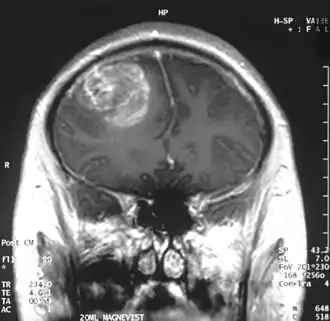

La tumeur peut prendre des apparences variées, en fonction de l'étendue de l'hémorragie ou de la nécrose, ou de son âge. Une scanographie (CT scan) montre généralement une masse non homogène avec un centre hypodense étendu en un anneau de taille variable entouré d'œdème. Il existe un effet de masse avec un déplacement possible du ventricule latéral et du troisième ventricule.

Le diagnostic d'un GBM suspecté lors d'un scanner ou une IRM repose sur une biopsie stéréotaxique ou une craniotomie, qui permet, par la même occasion, de retirer autant de tumeur que possible. Bien que la totalité de la tumeur ne puisse théoriquement pas être retirée, en raison de sa multicentricité et de son caractère diffus, une résection partielle peut tout de même prolonger légèrement l'espérance de survie.